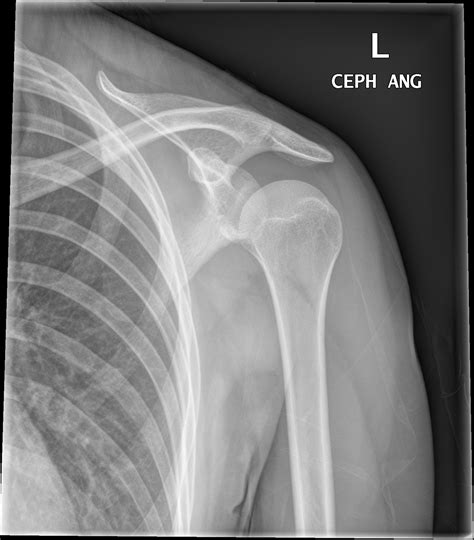

Interpreting a normal Xray of shoulder involves understanding the key anatomical structures visible in the images. A normal shoulder X-ray should show:

• Clear and distinct outlines of the humerus, scapula, and clavicle.

• Normal joint spaces without signs of narrowing or erosion.

• No evidence of fractures, dislocations, or bone spurs.

• Symmetrical appearance compared to the contralateral shoulder.

Here is a table outlining the key structures visible in a normal shoulder X-ray:

Structure Description

Humerus The long bone of the upper arm, which articulates with the scapula to form the shoulder joint.

Scapula The shoulder blade, which provides attachment points for muscles and ligaments.

Clavicle The collarbone, which connects the shoulder to the sternum.

Glenoid Fossa The socket of the scapula that articulates with the humeral head.

Acromion The bony process of the scapula that forms the highest point of the shoulder.